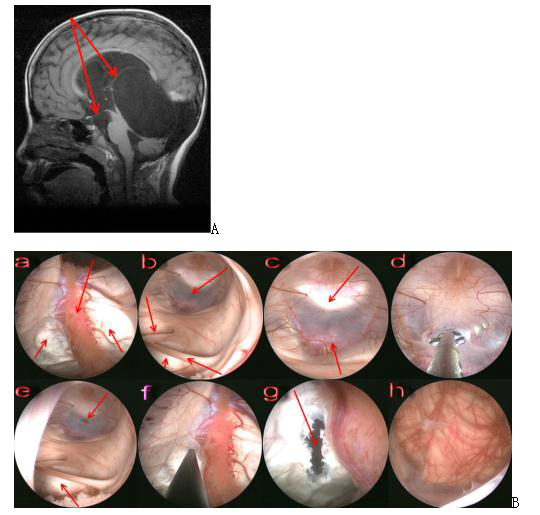

3. tetraploid pool cyst (preferred neuro-endoscopic surgical treatment)

Figure 7. A Preoperative magnetic resonance image shows the arachnoid cyst of the tegmental pool protruding upward into the lateral ventricle, with arrows indicating the direction of the fistula at the base of the third ventricle as well as the cyst-lateral ventricle fistula; B Intraoperative screenshot, endoscopic view of the surgical steps for the arachnoid cyst of the tegmental pool. a: endoscopic entry into the lateral ventricle, with bilateral arrows below indicating the top of the cyst protruding into the lateral ventricle and arrows above indicating the choroid plexus; b: endoscopic entry into the third ventricle, with the upper right arrow indicating the floor of the third ventricle, the lower right arrow indicating the middle mass being stretched and elongated, the upper left arrow indicating the superior port of the catheter being squeezed closed, and the lower left arrow indicating the wall of the cyst protruding into the third ventricle; c: floor of the third ventricle, with the upper arrow indicating the dorsal saddle and the lower arrow indicating the basilar artery; d: fistula of the floor of the third ventricle; e: after fistula of the floor of the third ventricle, with the upper arrow indicating the fistula f: fistula at the top of the cyst protruding into the lateral ventricle; g: arrow indicating the site of the fistula; h: endoscope entering the cyst through the fistula and the superior surface of the cerebellum below is visible.